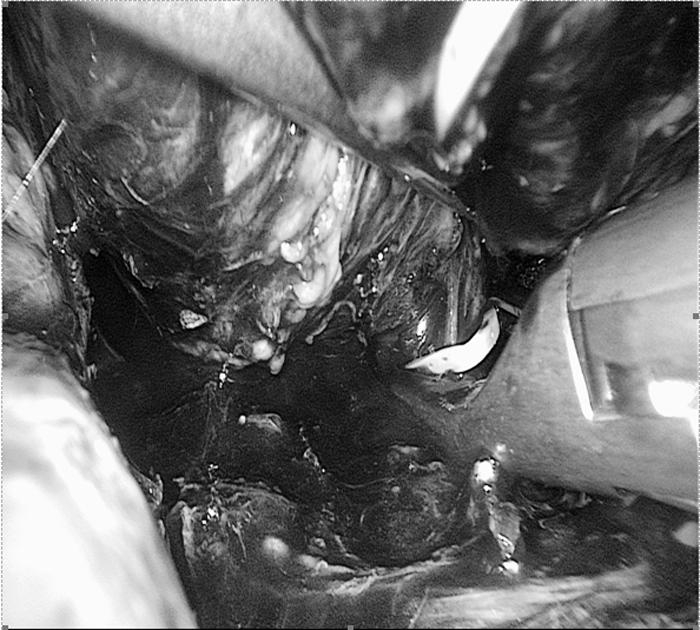

手術(shù)中影像(圖片已做處理)

??? 麻醉科余功敏主任醫(yī)師已經(jīng)和萬醫(yī)生配合完成了好幾臺嗜鉻細(xì)胞瘤的手術(shù)。手術(shù)當(dāng)日,余功敏在完成了深靜脈穿刺、動脈穿刺和氣管插管后,又在一旁準(zhǔn)備了自體血回輸設(shè)備,說:“你放心開始手術(shù)吧!”術(shù)中雖然經(jīng)歷了血壓飆升和血壓下降,但余功敏鎮(zhèn)定自若,降壓藥和升壓藥輪流上陣。經(jīng)過嚴(yán)密的麻醉監(jiān)護(hù)、精確的術(shù)中操作,一個小時后在腹腔鏡下有驚無險地順利切除腫瘤。手術(shù)順利,老太太術(shù)后恢復(fù)快,第五天就出院。